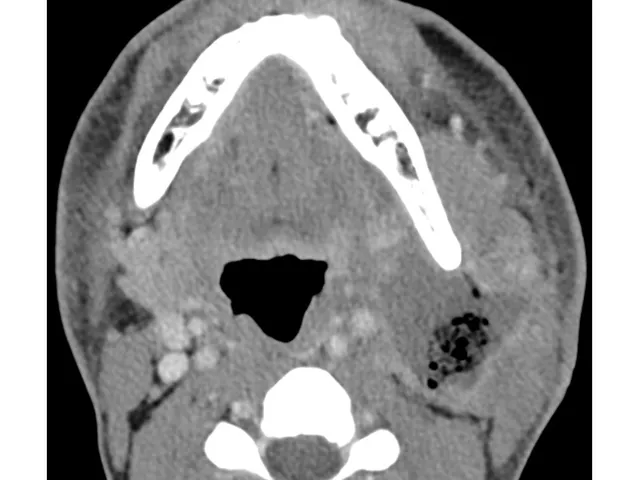

- Acute mouth disease for emergency radiologists

- The spaces of the neck and their relevance in the acutely ill patient

- Patterns of spread of infection in the neck and beyond